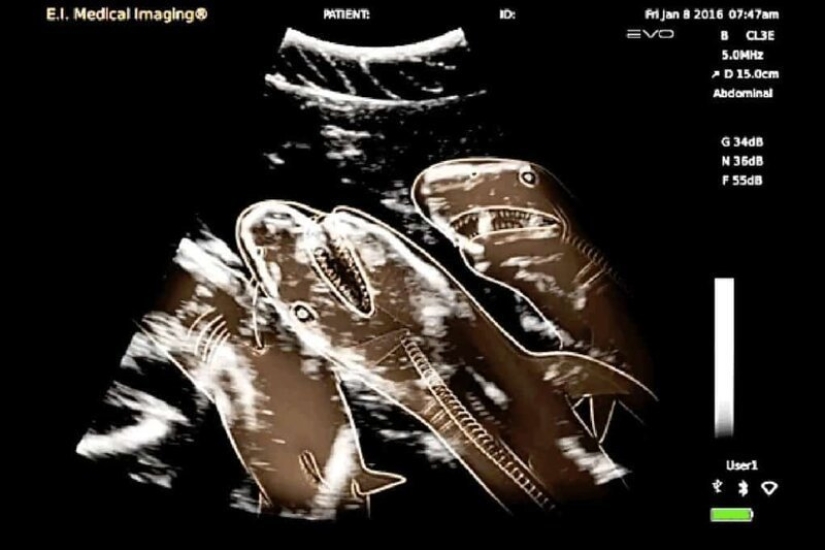

Ultrasound of a pregnant shark